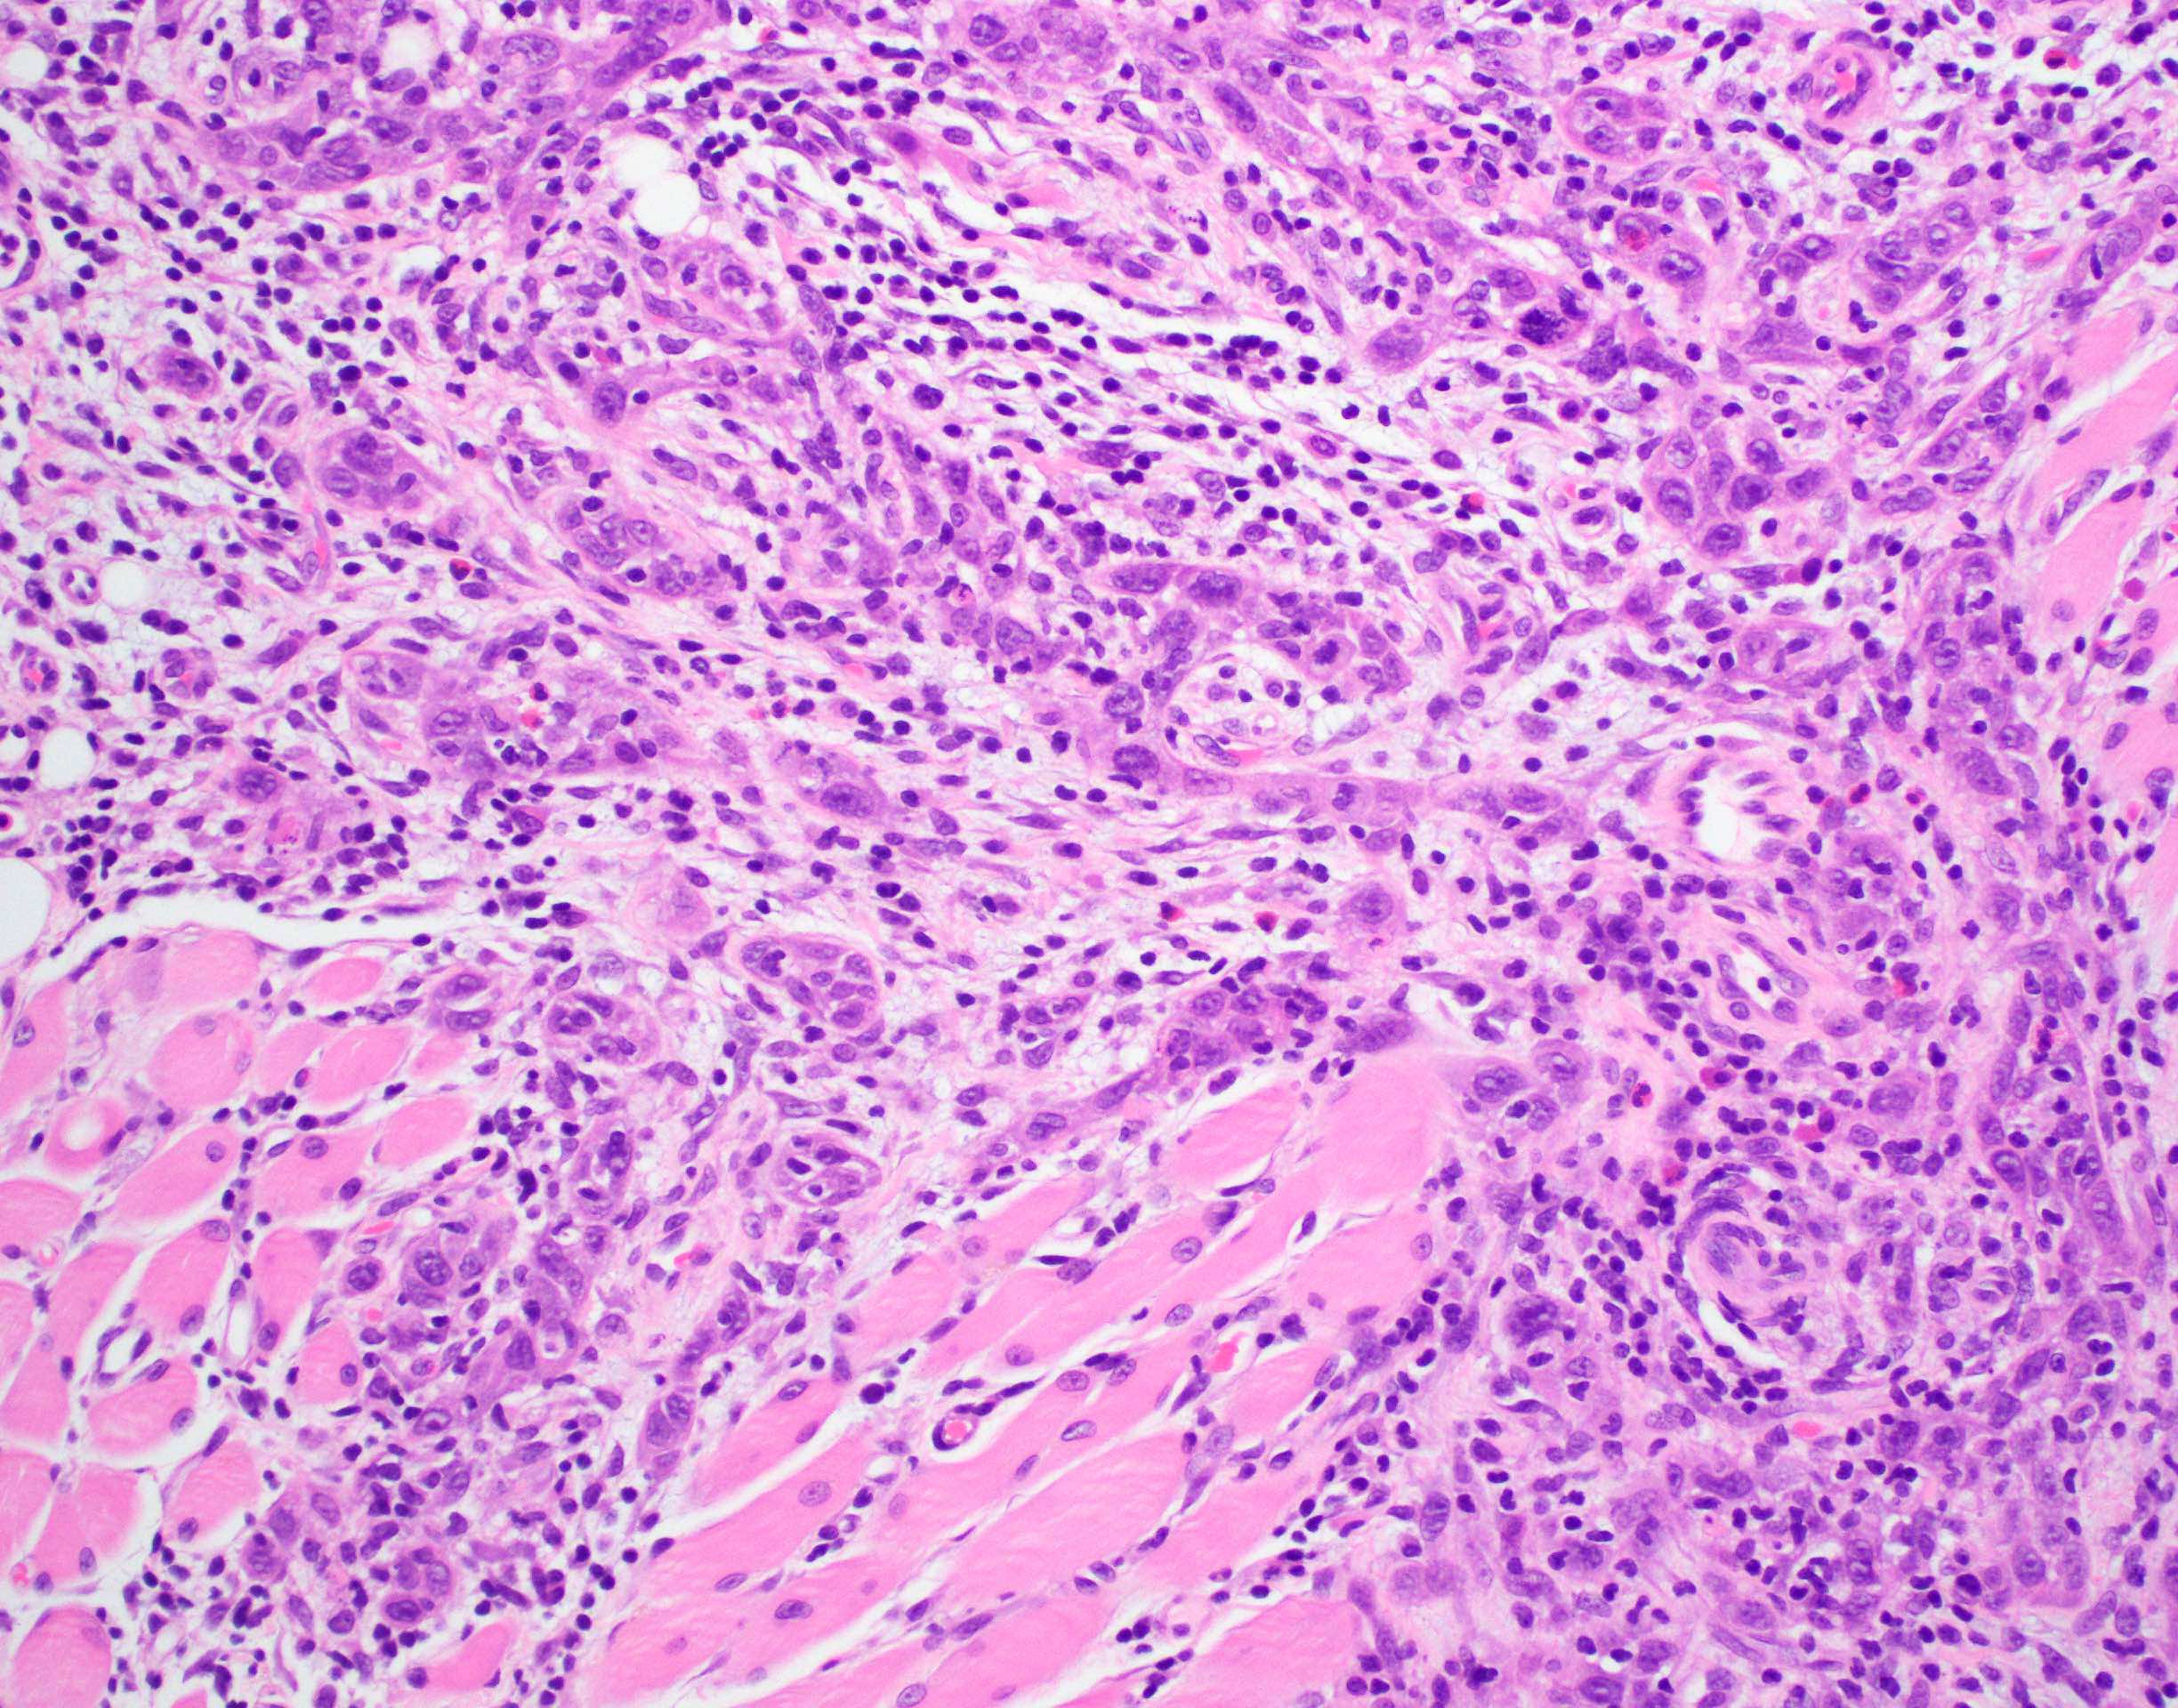

- Spindle cell / sarcomatoid squamous cell carcinoma (Am J Otolaryngol 2008;29:123)

- Most commonly occurs postradiotherapy or as second primary

- Mesenchymal in appearance

- Atypical plump spindled cells arranged in fascicles or storiform pattern

- May have metaplastic or neoplastic cartilage or bone

Microscopic (histologic) images

Contributed by Ruta Gupta, M.B.B.S., M.D.